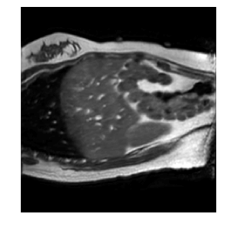

Qualitative results are shown in Fig. 4. We observe no large qualitative differences in the performances of MFIN and MFINc for either loss function. Since, MFINc-SSIM provides the best quantitative results, we show interpolated images from this method and compare them against SCIN-SSIM. Both methods perform well when the motion between the neighbouring images is low. This is reflected in the absence of any structures in the error images in Fig. 4.1. However, RMSE is lower for SCIN because it produces a denoised interpolated image, while MFIN carries over the noise pattern from the neighbouring known image. Whenever there exists high motion between the images being interpolated, SCIN produces blurry images and often misses image structures. This can be observed in cases 2-4 in Fig. 4. For all these cases, MFINc (and also MFIN) produces sharp images and largely preserves structures in the images. Fig. 4.2 shows a case where MFINc additionally has a much better performance with respect to image alignment. Fig. 4.3 shows a representative case, with small improvement in image alignment, yet worse RMSE and SSIM values for MFINc. Finally, Fig. 4.4 shows a case, where MFINc produces worse alignment of structures than SCIN.

1)

14.13, 0.81 13.02, 0.84

2)

9.16, 0.76 10.12, 0.74

3)

9.75, 0.85 12.94, 0.81

4)

a b c d e